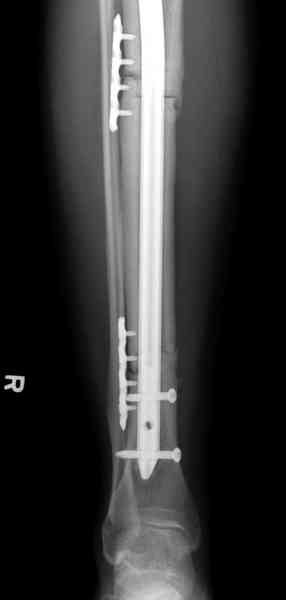

Недавно на нашей ежемесячной Morbidity&Mortality

conference мы разбирали похожий случай, ложный сустав большеберцовой кости после резекции опухоли.

К нашему онкологу-ортопеду обратился больной с жалобами на боли в голени, из рассказа - год назад была сделана биопсия большеберцовой кости, но название заболевания "не запомнил”.

Оперирован в военном госпитале с заменой сегмента

аллокостью большеберцовой кости и после демобилизации явился для постоянного наблюдения по месту жительства.

Наши имели проблему со сращением, пришлось им сделать динамизацию, дополнительную аутопластику.

Снимки представлены.